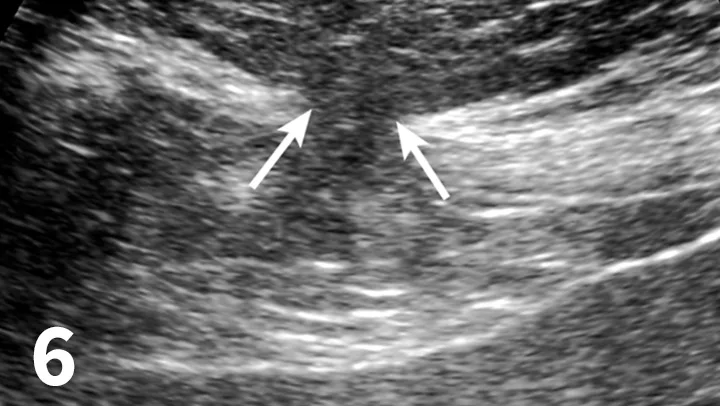

FIGURE 5

Lateral radiographic view showing tubular organ displacement into the subcutaneous tissues (arrows) from a ventral incisional hernia.

Imaging

• Plain films showing abdominal organ displacement into subcutaneous tissue at the wound site are diagnostic for an incisional hernia (Figure 5).